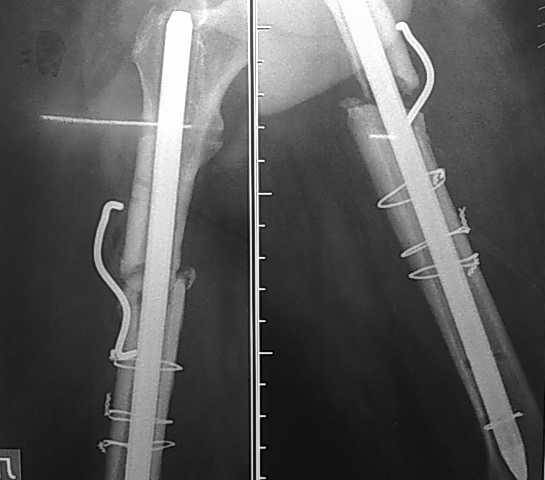

пациент 45 лет имел перелом бедра в 2006г плюс О.инфаркт. после лечения инфаркта - о\синтез

стержнями - перелом стержней с миграцией "туда-сюда" в канале кости. далее БИОС 12 стержнем

(канал 14). после динамизации синтеза - рецидив болей и патологич.подвижность. ввиду

отсутствия конструкций и финанс.положения пациента - реостеосинтез через 2 года ( за это

время 3 случая рожистого воспаления голени на этой же ноге) стержнем ЦИТО 14 размера с костной

пластикой "чипсами" и фиксацией скобой с памятью формы - результат на Рг-грамме через 3 мес.(

вес пациента 120кг). при введении стержня ЦИТО - после рассверливания до 14 диаметра - все

равно трещина в дистальном отломке. планируем БИОС 14 гводдем с блокированием в 2х

плоскостях и костную пластику из крыла или по Хохутову - НЕТ 14 СТЕРЖНЯ ТИПА ЭКСПЕРТ - НИГДЕ!!